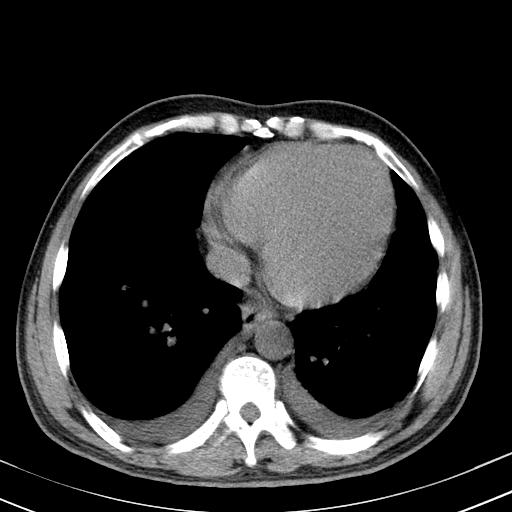

以下是引用zxl51642在2010-3-21 17:06:00的发言:[br]右下中心型肺癌并阻塞性肺炎/不张,纵膈淋巴结肿大,右侧大量胸腔积液,左侧少量胸腔积液,少量腹水。建议纤维支气管镜进一步检查。